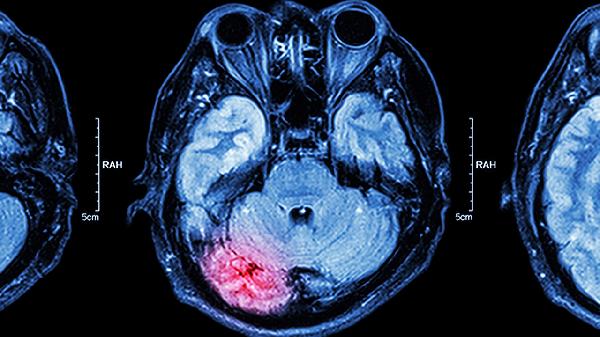

脑叶是大脑皮质的一部分,分为不同的叶状结构,如额叶、顶叶、颞叶和枕叶。切除脑叶是一种神经外科手术,具体情况取决于病变的位置和性质。手术一般会在全身麻醉下进行,可以通过开颅或使用微创手术技术进行,手术的目的可能是治疗癫痫、脑肿瘤、颅内损伤或控制其他相关的脑部疾病。切除脑叶可能带来疾病控制、症状改善、功能改变、风险和并发症等方面的效果和影响:

4、风险和并发症:切除脑叶是一项复杂的手术,可能伴随着一定的风险和并发症。术后可能出现感染、出血、癫痫复发或其他神经学问题。这些风险和并发症的具体情况取决于手术的复杂性、患者的整体健康状况以及术后的护理。